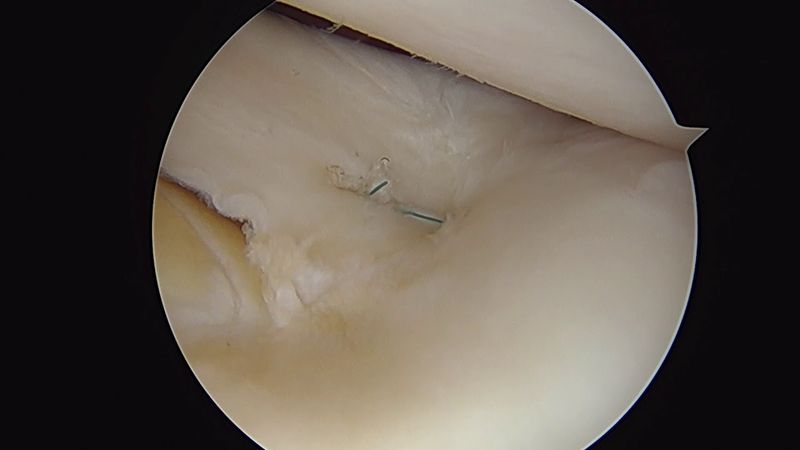

Arthroscopic bucket-handle lateral meniscal repair by Dr. Dold (all-inside technique)

Andrew Dold, MD - Orthopedic Surgeon發布日期: